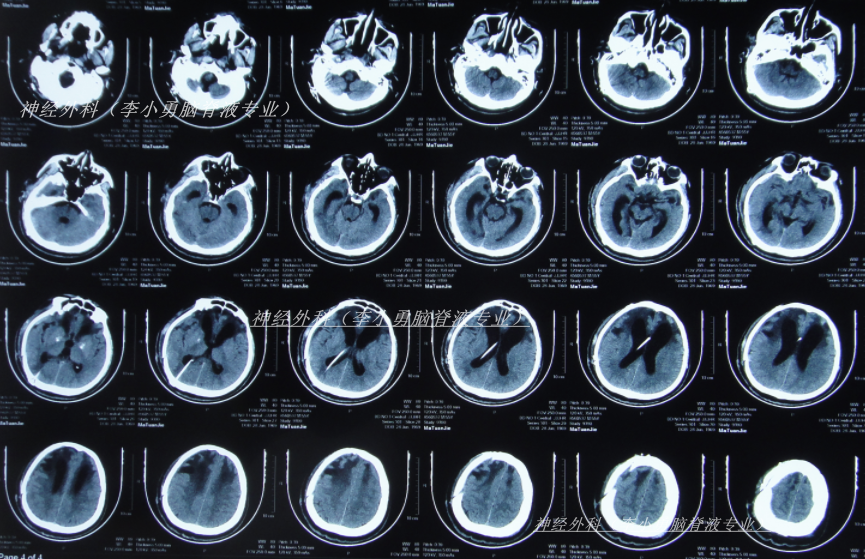

脑室腹腔分流术后28天即2024年10月17日,进行了颅骨修补术(图-3)。

图-3:2024年10月18日头颅CT

颅骨修补术后5天即2024年10月22日(脑室腹腔分流术后33天),查头颅CT示颅骨修补术后状态(图-4)。

图-4:2024年10月22日头颅CT